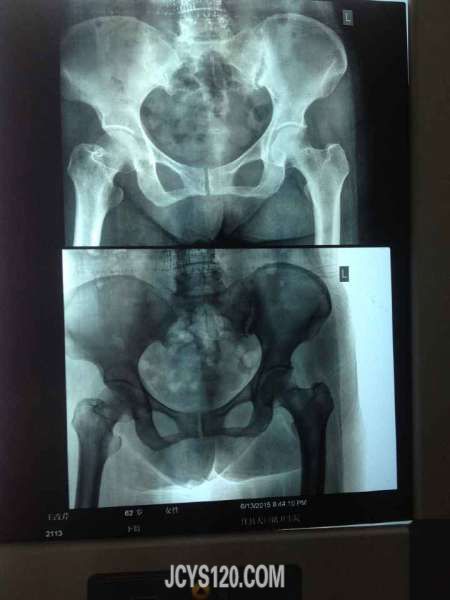

同行帮给看一下这个造影,需要怎么治疗比较理想

玻璃箱 2021-3-2